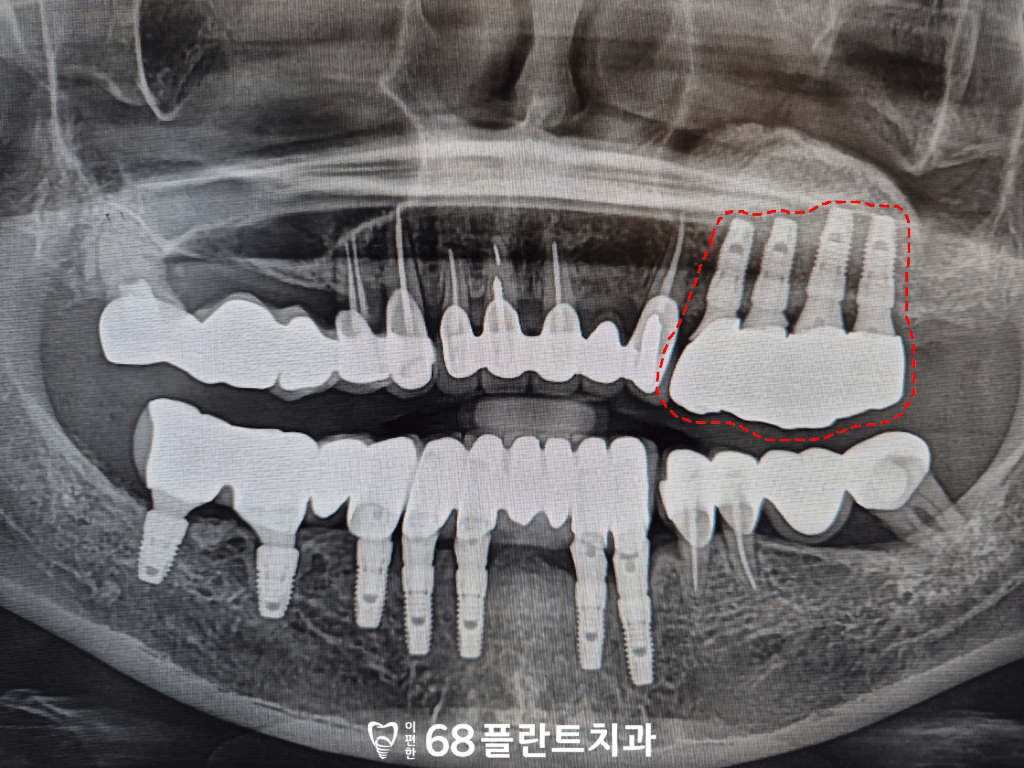

그래서 본원에서는

왼쪽 위 네 개의 치아를 발치 후,

상악동거상술을 동반한

임플란트 식립을 진행하기로

계획을 수립하였습니다.

이렇게 상악동거상술을 진행하여

부족했던 부위에 새로운 뼈를 형성한 후,

그 위에 임플란트를 식립함으로써

잇몸뼈가 녹아 사라졌던 자리에도

안정적으로 치아 기능을

회복할 수 있게 되었습니다.